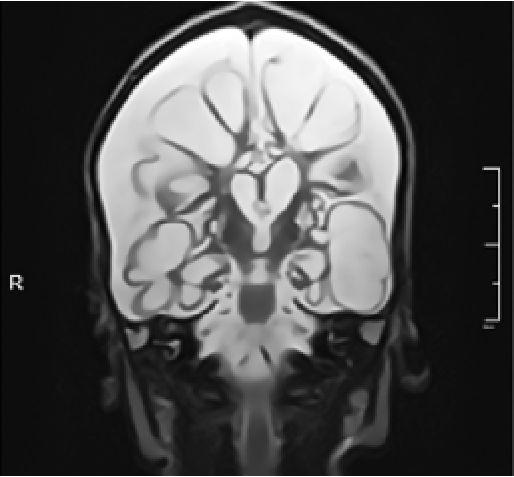

Рис. 6. Уменьшение объемов гиппокампов на фоне тотальной кистозной трансформации вещества головного мозга